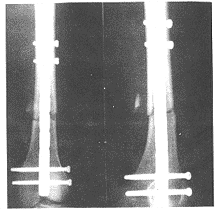

图2 股骨干骨折术前正、侧位X线片

图3 股骨髁上交锁钉术后正、侧位X线片

1.3 手术方法 麻醉满意后,取仰卧位。膝关节屈曲30°~40°以方便骨折的复位和固定。根据骨折类型决定开放或闭合复位。通过膝前中线切口和髌内侧关节囊进入膝关节。如有关节内骨折,先行开放复位,关节面要求解剖复位。然后在髁的前后位置横行固定2枚拉力螺钉,注意螺钉间保留足够的空间允许髓内钉进入髓腔。髓内钉的进钉点选在髁间窝,位置恰好在交叉韧带起点的前方。注意进钉点应位于二髁中央以防止内外翻。用开口器开一直径>所选用髓内钉直径1.0~1.5mm的入口。然后置换圆头导杆穿过复位的骨折部插入股骨干髓腔,先采用8.0mm直径,后依次再以0.5mm直径递增的扩髓器扩髓,直至扩髓器直径>所选髓内钉直径1.0mm。一般在股骨干峡部直径较小同时使用直径12mm或13mm髓内钉时需要扩髓。扩髓过程中注意保护髌腱。完成扩髓后,将髓内钉与瞄准器安装在一起,屈曲膝关节到45°~60°,沿导钉将髓内钉推入股骨髓腔,直到髓内钉尾沉入关节面下1~2mm。注意不能用暴力将髓内钉打入髓腔。如果复位和扩髓合适,髓内钉进入应该是很顺利的。然后先通过瞄准器固定2枚远端锁钉,再锁定近端的2~3枚锁钉以获得完全的稳定。如选用多孔型髓内钉,则根据骨折粉碎情况酌情固定多个螺钉(见图2,3)。术毕膝关节用无菌生理盐水大量冲洗 至清洁,并放置引流。本组手术时间60~130min,平均80min。